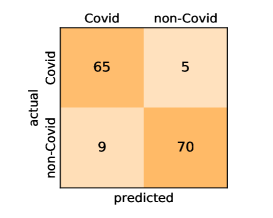

Here, we present and discuss the obtained results for detecting COVID-19 on the considered CT image datasets with different deep networks. We report the quantitative results along with the confusion matrices for every single architecture of the adopted networks.

On the SARS-CoV-2 CT dataset, ResNet101 achieves the best overall performance with respect to almost all evaluation metrics, with an average accuracy and F1-score of and , respectively. The model also achieves an average sensitivity rate of indicating that, on average, only two COVID-19 images are falsely predicted as negatives. It is also powerful enough to correctly identify all Non-COVID-19 cases with only one false positive resulting a specificity rate of . The highest sensitivity score of is achieved by the InceptionV3 model, where only one COVID-19 image is falsely predicted as negative on average. The SqueezeNet model obtains the lowest performance with respect to all evaluation metrics with a fairly acceptable average accuracy and sensitivity scores of and , respectively. Also the ShuffleNet architecture obtains satisfactory performance with approximately improvements on average for all metrics compared with SqueezeNet. Although the results obtained by these models are inferior compared with the rest of models, but they are more efficient. This matches their main objective of reducing the computational costs rather than improving their visual recognition abilities. The rest of models achieve competitive performance and very promising results with slight performance differences. Comparing the different variants of ResNet and DenseNet, we can see that the deeper variants from each architecture yield a slightly better performance. The deeper ResNet101 and ResNeXt101 show a marginal gain in performance compared with their shallower counterparts. The details about class-wise results for each model are summarized in the confusion matrices in Figure 9.